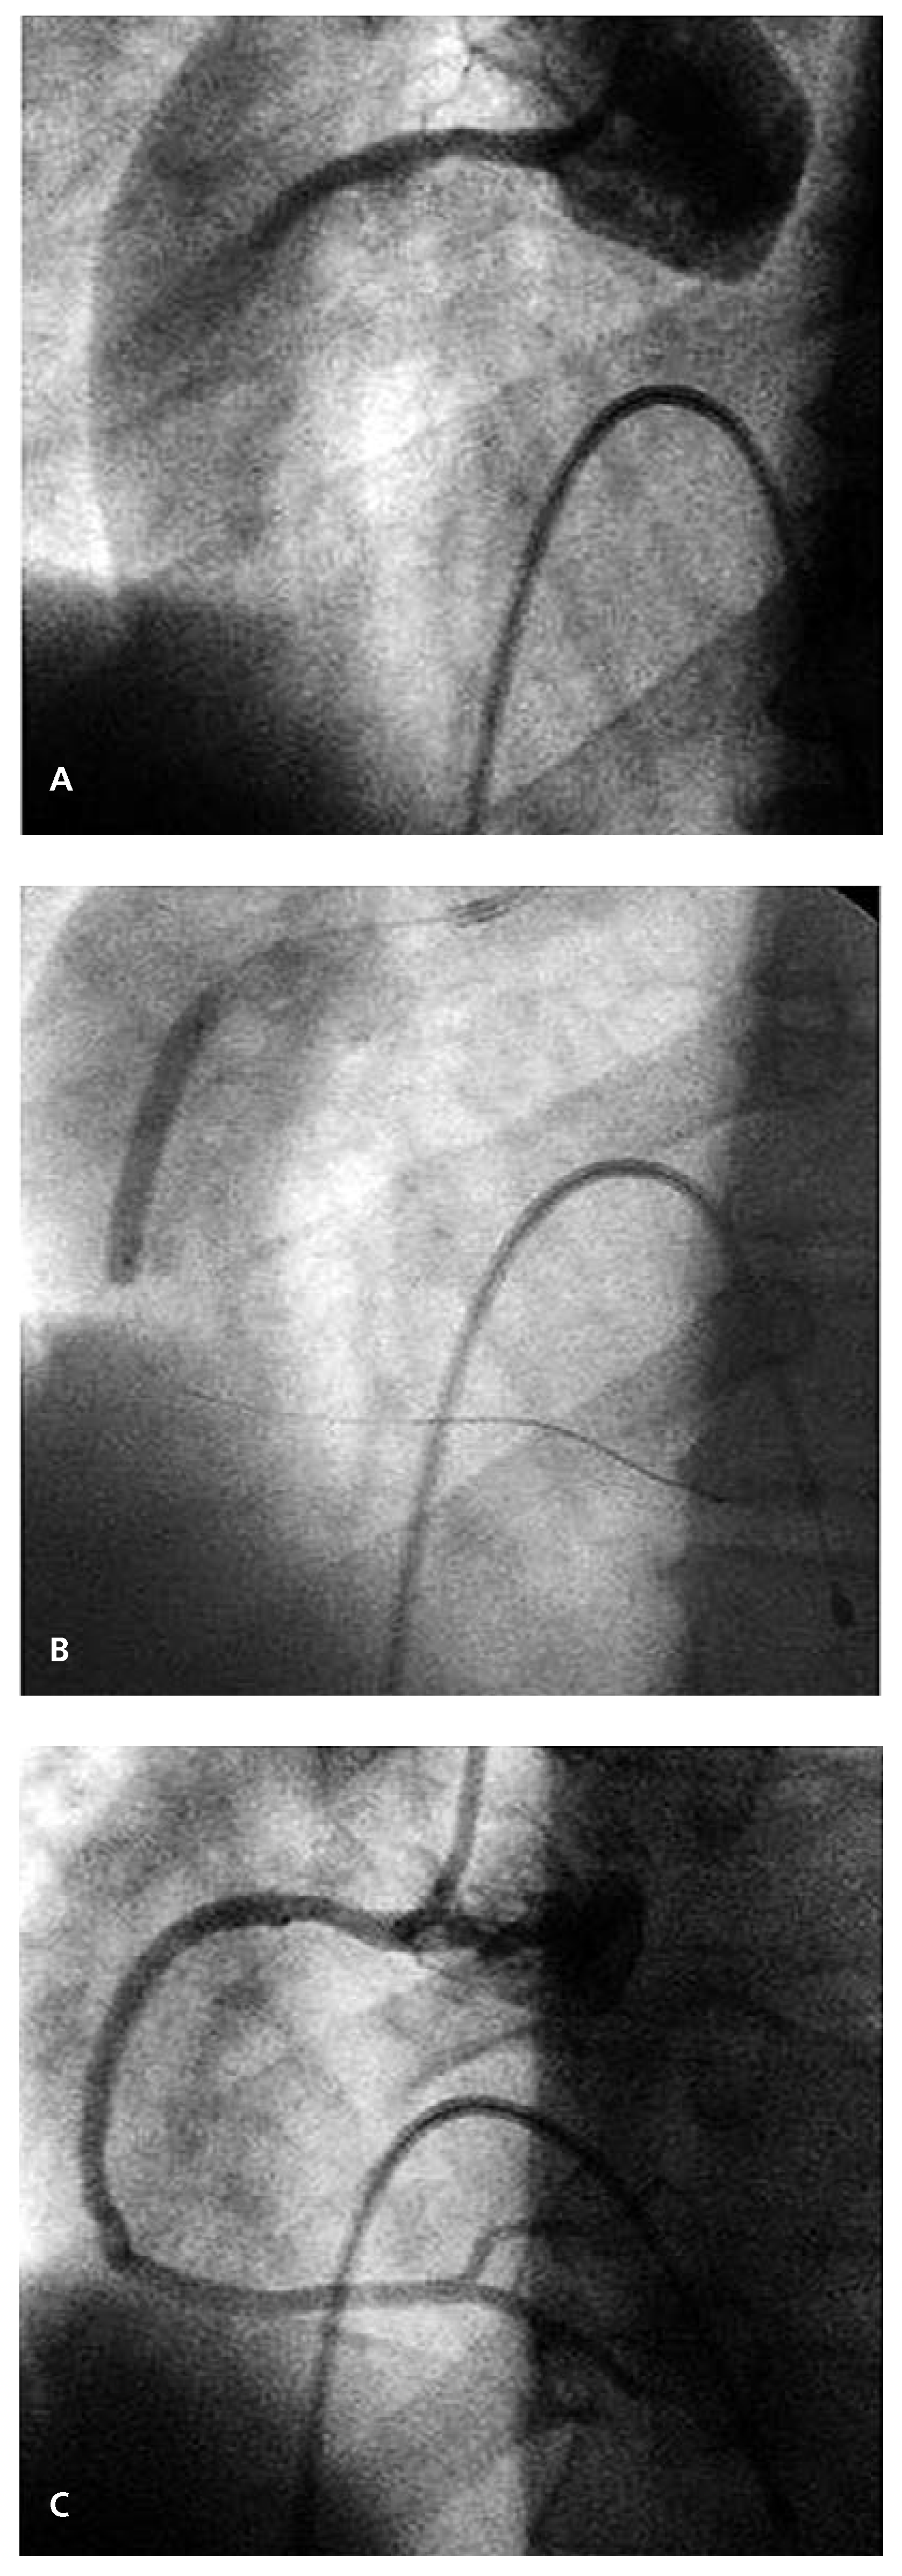

Acute Stent Thrombosis Due to Absence Without Leave (AWOL)

Case report